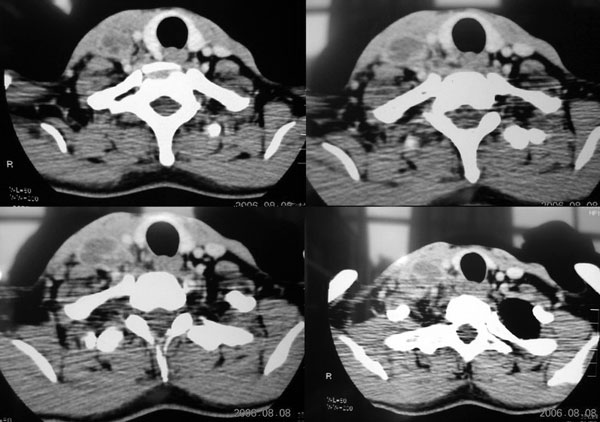

右颈部肌肉、血管间隙内可见不规则肿块,强化后呈多房性,间隔及壁线样强化,考虑颈部脓肿。

标题: 结果

穿剌抽吸乳白色液体6ml,实验室检查为炎性细胞。谢谢大家精彩分析!

颈部血管间多房囊性肿块,边缘模糊,增强囊壁有强化,中间低密度区无强化。从强化特点支持颈部神经鞘瘤及淋巴性肿瘤。但病人病史较短,且有高热,病灶边缘模糊,又都不支持。神经鞘瘤及淋巴性肿瘤多边缘清楚。因此还是考虑炎症。